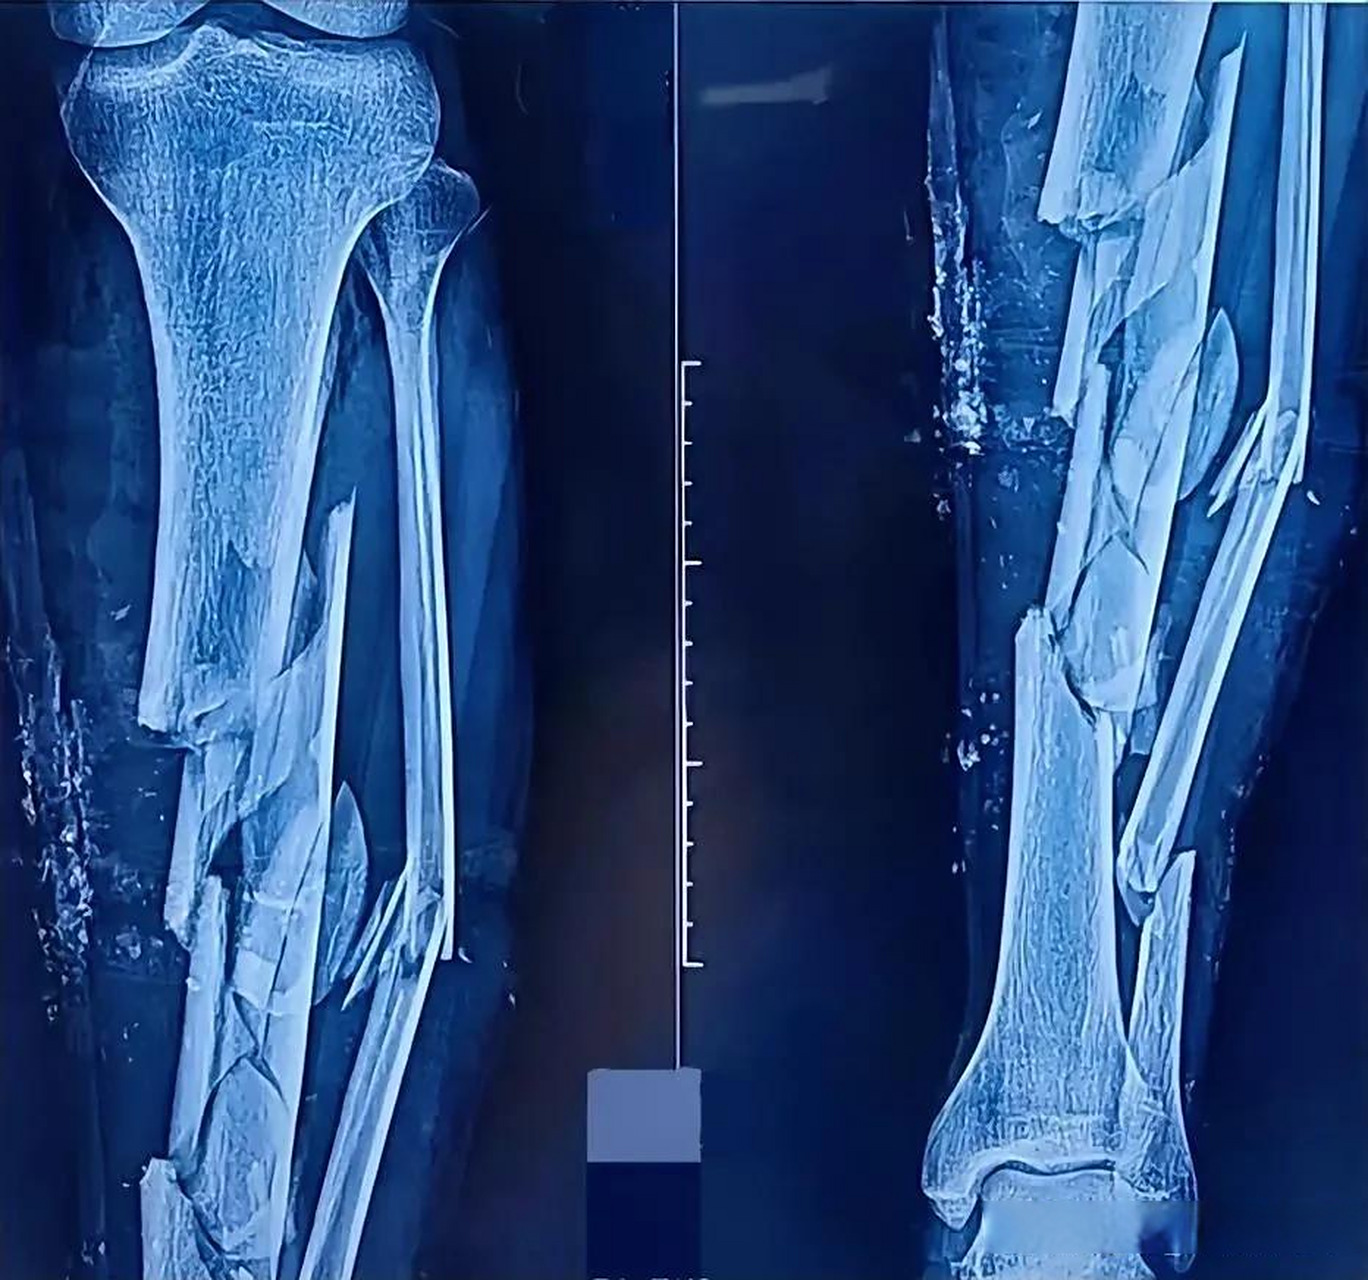

胫腓骨粉碎性骨折

一例严重胫骨粉碎性骨折,请大家讨论下一步治疗方案? [病例帖]

看看这个胫腓骨远端开放性粉碎性骨折治疗

左胫腓骨粉碎性骨折

请教胫骨开放性粉碎性骨折的治疗

胫骨远端长螺旋形粉碎性骨折

右胫腓骨粉碎性骨折行髓内钉请批评指教

胫腓骨远端粉碎性骨折求手术方案 [病例帖]